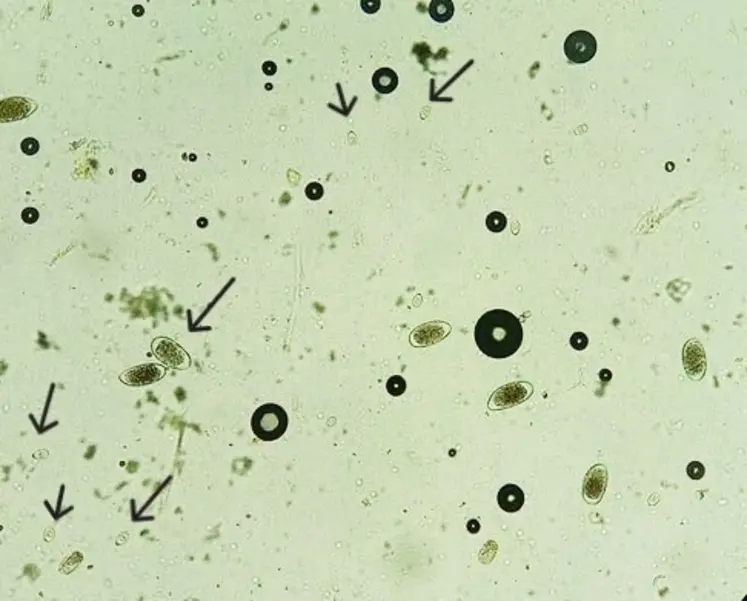

Une coproscopie avec de l’eau salée met en évidence des milliers d’œufs de type Eimeria bovis.

De retour au cabinet, nous réalisons une coproscopie avec de l’eau salée. Nous mettons alors en évidence des milliers d’œufs de type Eimeria bovis, ce qui confirme la présence de coccidiose pathogène. Nous conseillons donc à l’éleveur un traitement à base de triazinone sur ce veau et ceux du même lot présentant un mauvais GMQ. Cette famille de molécules est utilisée à la fois en préventif et en curatif. En fonction du traitement, la rémanence sera différente, ce qui est à adapter à chaque élevage.